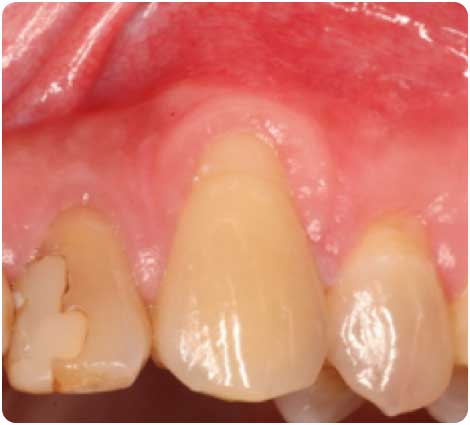

牙根覆蓋

初診問題:

30歲男性,矯正前處理牙齦萎縮的左上犬齒

解決方式:

圖為術前與術後三個月